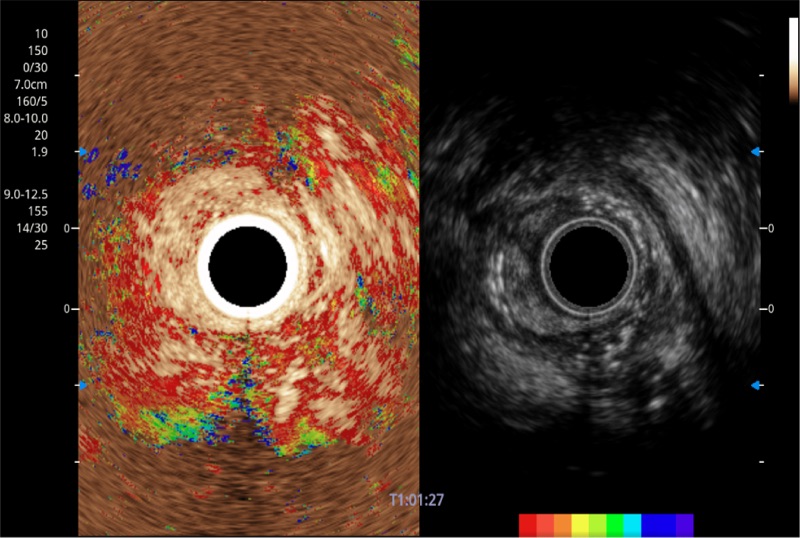

可人为将灰阶图像转变成彩色的显示方式,增强人眼对于不同回声强度的敏感度,主观上增加了图像分辨率

具有四种造影成像效果

食管内间质瘤清晰显像